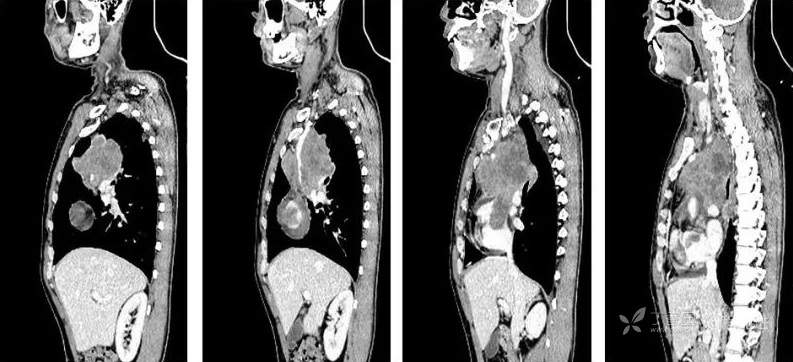

CT

平扫CT值约38HU,动脉期CT值约46HU,静脉期CT值约58HU